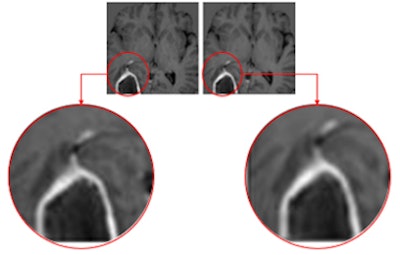

IB Zero G accepts noncontrast medical images as inputs and produces a synthetic image series that mimics contrast-enhanced images of comparable diagnostic quality, IB said. Benefits include less time in the scanner for patients and for providers, an increase in scanner availability, and a reduction in gadolinium expense, the company reported.